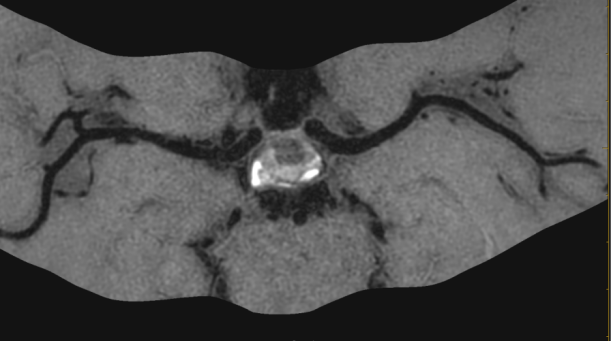

1招丨精准识别不稳定斑块

4df07320cb4936fc878ee04289f17171.png

以上4图平扫的T1W-VISTAT2WT1W-3D-SNAP都发现大脑中动脉M1段的大小为1.2*1.5*2.8mm等低信号斑块。

6c7180e7ed935be81a1d0dac685b2bb3.pngf8d20e7e820aa9111b30f3e48b62d51c.png

上图是打药后扫描的T1W-VISTA+C图像,斑块表现为轻度强化,综合考虑为不稳定斑块。这种情况需要慎重处理,斑块破裂和脱落风险比较大,建议经药物治疗后随访复查。